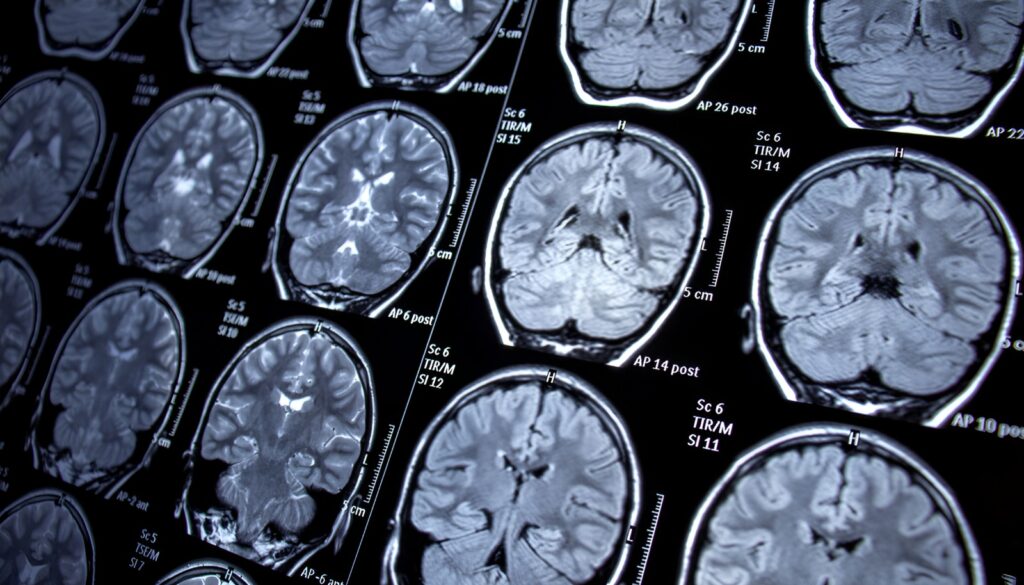

Al contrario, la risonanza magnetica per immagini (RMI) è più ampiamente disponibile, non invasiva ed economicamente vantaggiosa, il che la rende uno strumento prezioso per rilevare la neurodegenerazione correlata all’Alzheimer e monitorare la progressione e la prognosi della malattia.

‘TRACE4AD’ analizza automaticamente risonanze magnetiche cerebrali e i test neuropsicologici per aiutare i medici a formulare diagnosi tempestive e personalizzate.